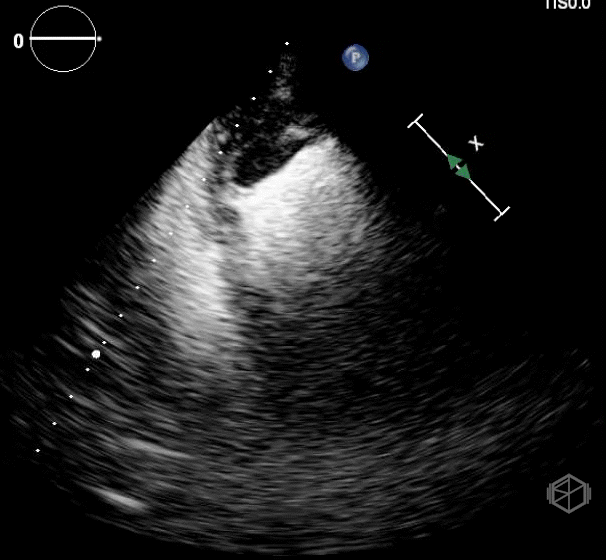

Dr. Frayberg saw this on her echo:

This patient has a significantly reduced ejection fraction, around 15%, with a heterogenous appearing mass at the apex of the left ventricle consistent with an apical thrombus. Normally contrast is used to see apical thrombi but since this was so large it was fairly obvious the patient had an LV thrombus.

Diagnosis: Heart failure with reduced ejection fracture, large apical thrombus

• Thrombi can be hyperechoic, isoechoic, or hypoechoic. A thrombus is usually homogenous with irregular borders and fills in the apex of a ventricle or attaches to the chamber wall or valves of atria.

• Transthoracic echo is usually enough to detect ventricular thrombus. Echo contrast may be used to delineate ventricular borders and identify a thrombus easier.